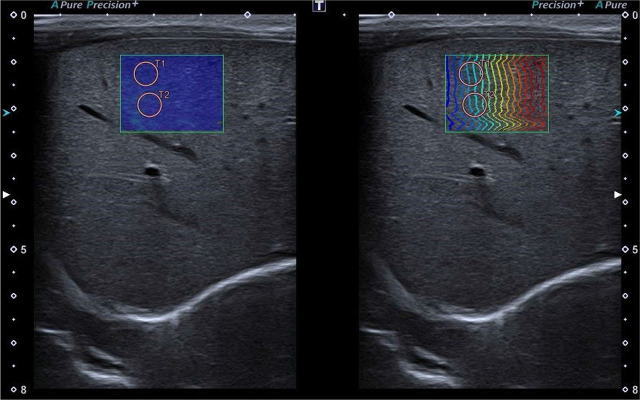

Materials and methods: We performed two-dimensional shear wave elastography of the liver, spleen and kidneys using a linear transducer at least 60 minutes after food intake in a group of 58 healthy, full-term, spontaneously breathing newborns. A series of 5 measurements using 5-mm-diameter regions of interest were performed, with the results expressed in m/s and kPa. Exam feasibility was assessed using the IQR/Median ratio as ≤30% for kPa, and ≤15% for m/s. Descriptive statistics, Shapiro-Wilk W, Levene's, Mann-Whitney U tests and Spearman correlation analysis were used for statistical assessment.

Abstract Image